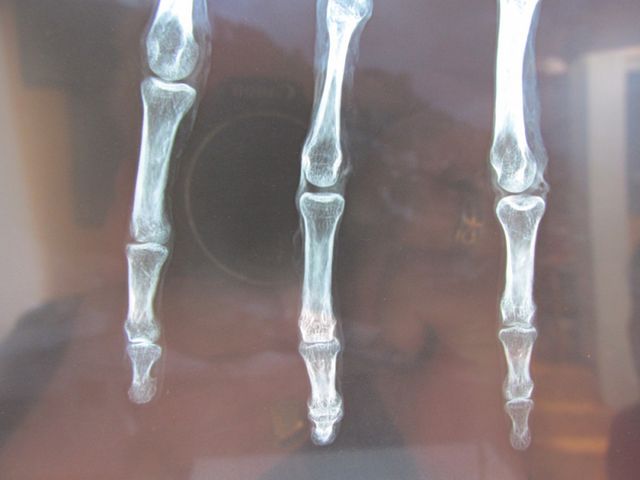

Археологи знайшли у одній із печер Перу руку з трьома пальцями.

Ренгтен показав, що будова пальців суттєво відрізняється від людських. Генетики планують в найближчий час зробити аналіз ДНК. При огляді експерти з'ясували, що на руці є перелом на долоні, а також виявили металевий предмет у шкірі.

Науковці планують найближчим часом провести аналіз фрагмента, щоб визначити, кому він належав.